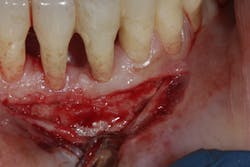

- Proper surgical technique including incision, flap design, and complete detoxification of bony defect and root apices (figures 3 and 3a)

- Primary closure without tension (figure 5)